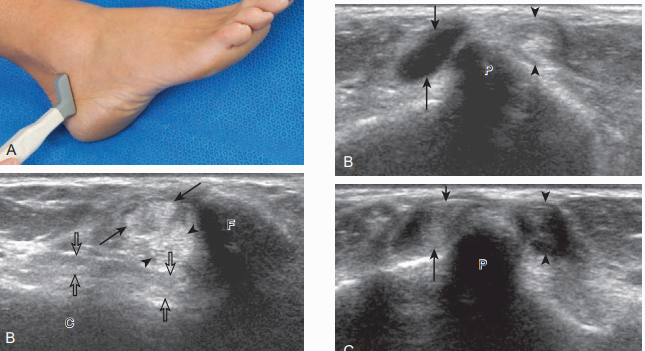

발꿈치종아리인대를 보기 위해서는 종아리뼈끝과 발꿈치뼈의 뒤 사이에 탐촉자를 세로방향으로 놓는다. 이 인대는 종아리근힘줄보다 깊은 곳에서 종아리뼈와 발꿈치뼈의 뒤-가쪽사이를 연결한다. 비등방성 때문에 정상적인 발꿈치종아리인대가 낮은 에코로 보여서 종아리근힘줄과 관계된 신경 절낭(ganglion cyst)으로 오인할 수 있다.

발목관절의 가쪽에 있는 인대를 검사하기 위해서는 먼저 탐촉자를 발목관절 가쪽에서 가로축방향으로 먼 쪽 종아리뼈 위에 놓는다. 탐촉자를 아래로 이동시키면 목말뼈가 보이는데, 이 위치에서 앞목말종아리인대는 종아리뼈와 목말뼈 사이에 비스듬히 놓여서 비등방성 때문에 낮은 에코로 보인다. 비등방성을 없애기 위해서 탐촉자를 인대에 대해 평행하게 놓으면, 앞목말종아리인대는 종아리뼈와 목말뼈 사이를 연결하는 가는 섬유의 높은 에코로 보인다.

비등방성은 인대를 확인할 때 도움이 되는 중요한 소견이며, 낮은 에코로 보이는 인대는 주변 지방조직의 높은 에코에 비해서 뚜렷하게 보인다. 인대가 확인되면 비등방성을 최소화하여 인대를 다시 확인하는 것이 꼭 필요하다.